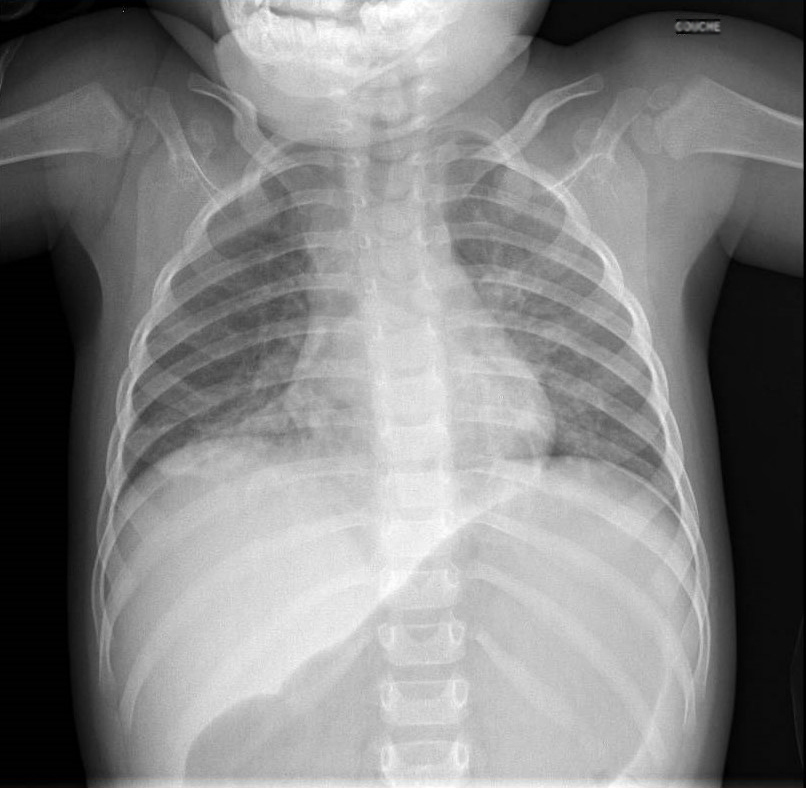

Voici la radiographie de thorax réalisée chez Simon :

Question 12 : Interprétez ce cliché.

Absence d’horizontalisation des côtes, moins de 8 espaces intercostaux, pas d’aplatissement des coupoles diaphragmatiques

Image typique des pneumopathies d’inhalation. Présence d’un bronchogramme aérien

L’image du lobe supérieur droit correspond au thymus

Index cardiothoracique 0,5